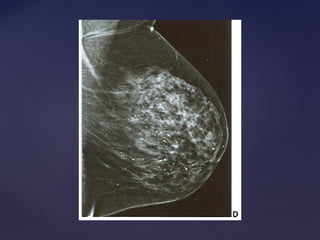

Padrão mamográficoPadrão mamográfico